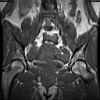

bekken